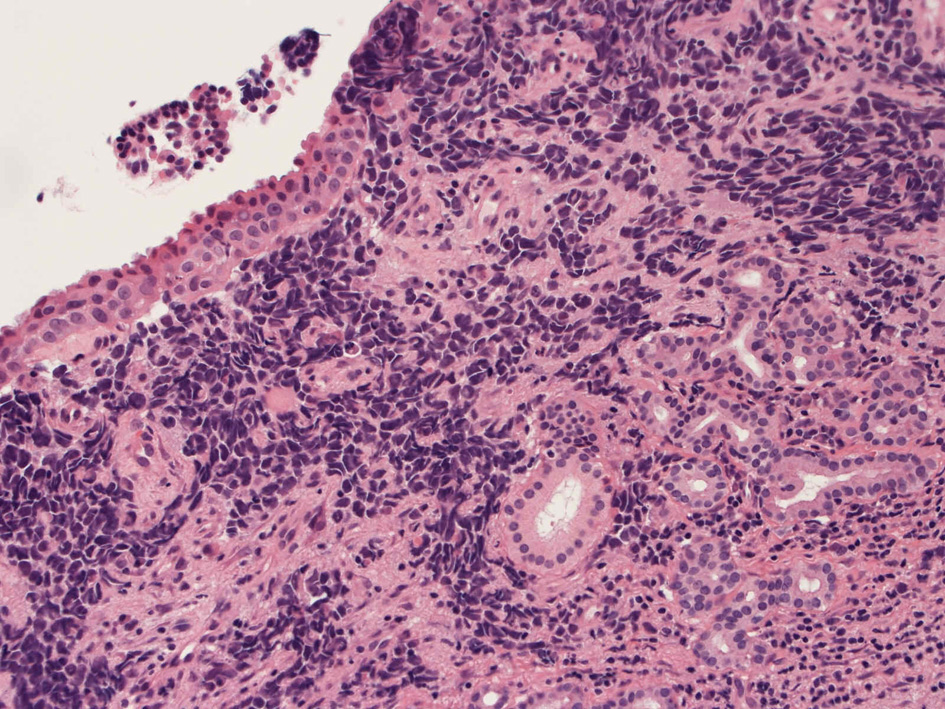

40歳女性 鼻粘膜腫瘤

右頸部のしこりを自覚。近医MRIで頸部多発リンパ節腫大あり当院を紹介される。右顎下, 右鎖骨上窩にも多数のリンパ節を触れる。穿刺細胞診ではcarcinoma疑い。右鼻腔, 上顎洞にも腫瘤が認められリンパ節腫大との関係を調べるために鼻腔腫瘤の生検が行われる。

病理組織所見